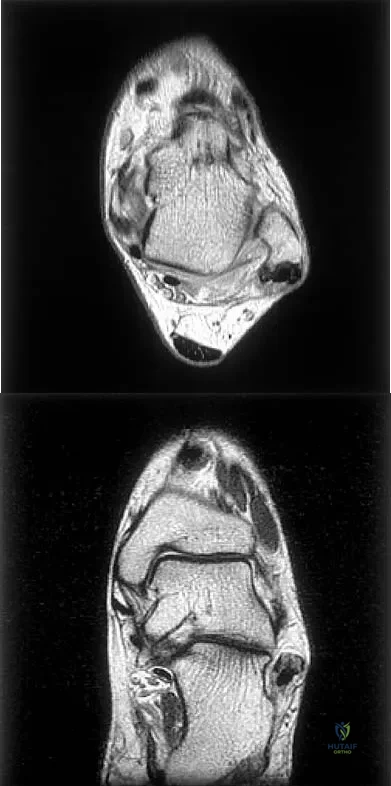

Figures 5a and 5b show axial and coronal MRI images of the left ankle of a patient with lateral ankle pain. What is the most likely diagnosis?

Explanation